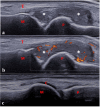

The interest and application of musculoskeletal ultrasound (MSUS) in juvenile idiopathic arthritis (JIA) are increasing. Numerous studies have shown that MSUS is more sensitive than clinical examination for detecting subclinical synovitis. MSUS is a well-accepted tool, easily accessible and non-irradiating. Therefore, it is a useful technique throughout JIA management. In the diagnostic work-up, MSUS allows for better characterizing the inflammatory involvement. It helps to define the disease extension, improving the classification of patients into JIA subtypes. Moreover, it is an essential tool for guiding intra-articular and peritendinous procedures. Finally, during the follow-up, in detecting subclinical disease activity, MSUS can be helpful in therapeutic decision-making. Because of several peculiarities related to the growing skeleton, the MSUS standards defined for adults do not apply to children. During the last decade, many teams have made large efforts to define normal and pathological US features in children in different age groups, which should be considered during the US examination. This review describes the specificities of MSUS in children, its applications in clinical practice, and its integration into the new JIA treat-to-target therapeutic approach.